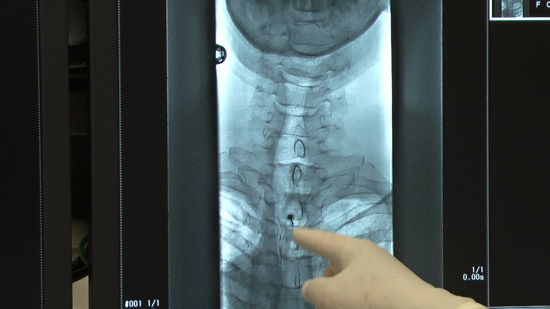

(2)穿刺部を透視画面と合わせて確認し、位置決めを行う。

(4)抵抗消失法にて硬膜外穿刺を行う、透視画面で確認。

※造影剤を注入し更に確認。同時に確認画像を撮影。

透視画面で確認。

今回は10cc注入時に患者さんに自覚体調を確認、更に投影画像を撮影。

注入終了時に投影画像を撮影。